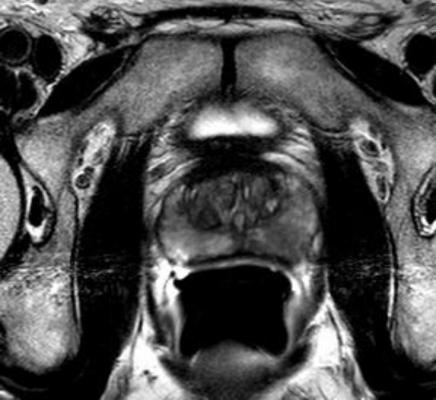

MR-US Fusion Biopsy to Diagnose Prostate Cancer: First 1,000 Men at UCLA — Evaluating the first 1,000 men who underwent mpMRI and MR-ultrasound (MR-US) fusion prostate biopsy between 2009 – 2014, researchers at University of California-Los Angeles found that among those who had MR-US, an increased risk of finding prostate cancer was directly related to age, MRI findings, PSA and PSA density. The most powerful predictor was the MRI, as high-risk prostate cancer was found in most men with highly suspicious (grade 5) MRI lesions. Both mapping and targeted biopsy were required for maximum detection of high-grade prostate cancers.

Comparison of MRI-US Fusion Targeted Biopsy and Systematic Prostate Biopsy: Single Institution Experience in 604 Patients — MRI fusion targeted biopsy (MRF-TB) detects more high-grade prostate cancer (Gleason greater than or equal to 7) and less Gleason six cancers than a systematic 12-core biopsy, according to new research from New York University (NYU) and New York Hospital. Researchers identified 604 men undergoing mpMRI prior to prostate biopsy since June 2012, to evaluate the potential of MRF-TB to discriminate between clinically significant and insignificant prostate cancer. MRF-TB detected more Gleason greater than or equal to 7 cancers and fewer Gleason 6 tumors, suggesting this biopsy technique may be more effective in helping to reduce over-detection of lower risk tumors.

Should a Normal Multi-Parametric MRI Preclude Prostate Biopsy? — According to researchers at University of California-Los Angeles, men with an elevated PSA level should consider a prostate biopsy even if a mpMRI appears normal. mpMRI is utilized to provide detailed anatomical and functional information so patients and urologists can make the most informed decision regarding prostate cancer diagnosis and treatment. mpMRI is the best modality for imaging localized prostate cancer but does not have 100 percent accuracy and therefore can still miss clinically meaningful cancers.

Examining data from 244 men who underwent mpMRI and ultrasound-guided biopsy between 2009-2014, researchers found:

- mpMRI failed to identify 16 percent of men with high grade cancer (Gleason score greater than or equal to 7); and

- Forty-seven percent of patients with no "region of interest" on mpMRI were found to have a Gleason score equal to or greater than six on their biopsies; this was more likely among patients with smaller prostates and prior positive biopsies.

MRI is an important tool for detecting the presence of prostate cancer and targeting prostate biopsies. However, this data suggests a normal mpMRI may still miss high-grade cancers. A biopsy should still be considered for patients with an elevated PSA suspicious for prostate cancer, even in the setting of a normal MRI.